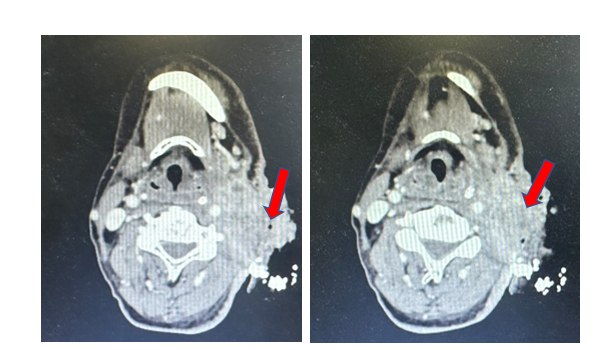

Hình 4. A. Sau 3 chu kì điều trị; B. Sau 6 chu kì điều trị

Sau 6 chu kỳ, bệnh nhân cải thiện nhiều trên lâm sàng: tăng 3 kg, có thể vận động vùng cổ và sinh hoạt bình thường, không còn triệu chứng đau, tổn thương sùi loét biến mất, chỉ còn sẹo trên da.

Trên hình ảnh cắt lớp vi tính: sau 6 chu kỳ điều trị, kích thước khối u giảm từ 71x60mm (trước điều trị) xuống 32x25mm, đánh giá bệnh đáp ứng một phần theo tiêu chuẩn RECIST 1.1

Hình 5. A. Trước điều trị; B. Sau 3 chu kì điều trị; C. Sau 6 chu kì điều trị

Sau 6 chu kì CF + Pembrolizumab, bệnh nhân được chuyển sang duy trì Pembrolizumab 200 mg truyền tĩnh mạch, chu kì 21 ngày.